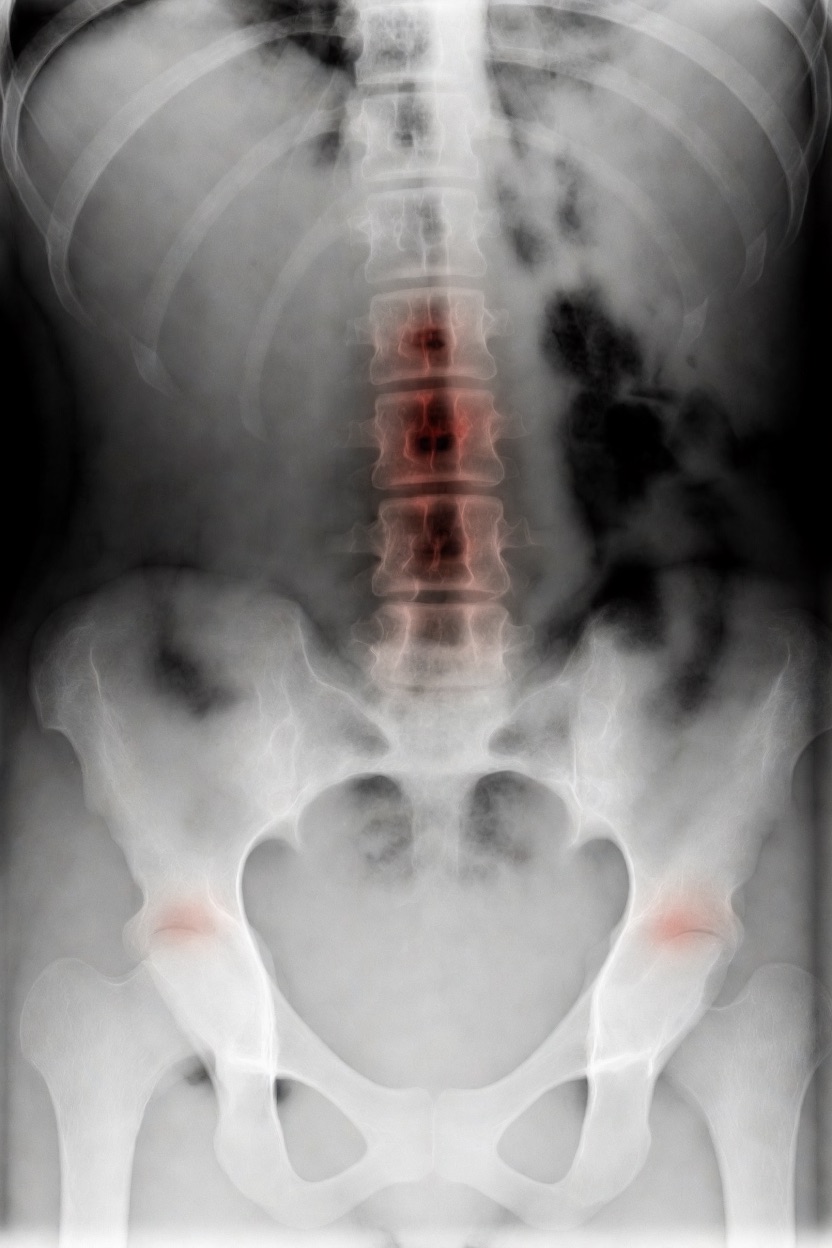

アートや写真の編集用に設計されたFlux Kontextのようなモデルを、医療画像、たとえば「単純な」骨折の赤色マーキングに使用できるか?

即答:面白い結果を出すが、過剰に反応し、医療ツールとしては信頼性に欠ける。これはアイデアを試すためのプロトタイプに過ぎない。

さらに攻撃的な設定(例:rk beta57、Denoise 1.0)では、**偽陽性100%、検出100%**という馬鹿げた結果に:すべてを赤で塗りつぶし、健常部もほぼすべて骨折と誤認する。未経験の目には区別がつかない。

重要

このLoRaは視覚的実験用のみです。

医療機器ではありません。信頼性がなく、臨床診断には使用しないでください。